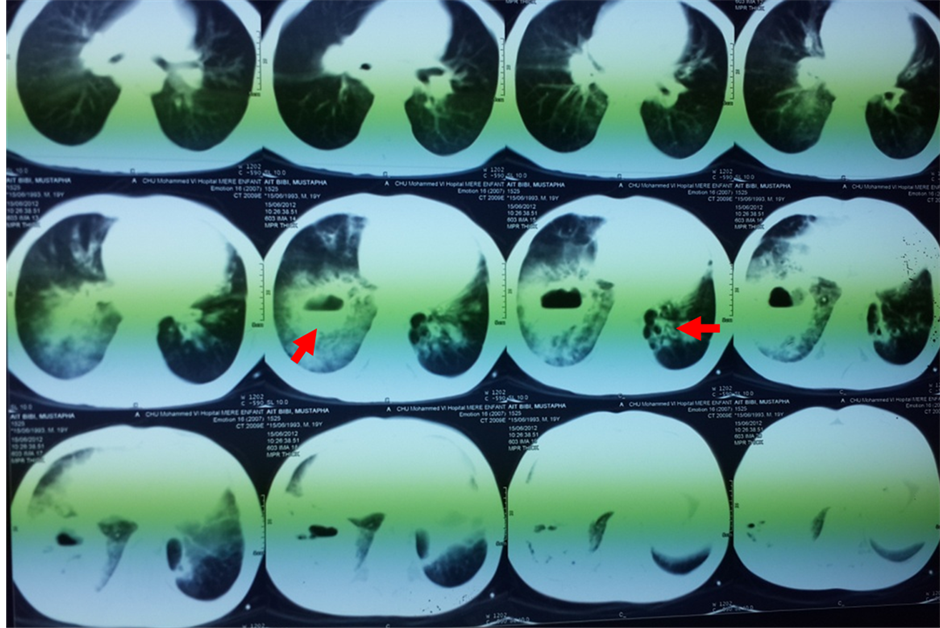

A 19-year-old North African patient, born of a non-consanguineous marriage, is the eldest in a family of three, his two brothers are healthy. He was admitted in an array of severe pneumonia consisting of nux and moderate hemoptysis and right chest pain in context of fever sensations and decline in general health. In its history, it was found a notion of recurrent and dragging respiratory infections on a plot of bronchiectasis with a psychomotor retardation discovered at the age of 7 years old. Clinical examination noted polypnea to 35 cycles/minute (normal respiratory rate is 16 - 20 cycles/minute), a blood pressure at 110/60 mm Hg (the normal rate is <120 mmHg for systolic and <80 mmHg for diastolic), a fever at 39.8˚C, an oxygen saturation of 96% (normal rate is between 95% and 100%), and incomplete condensation syndrome in right basi-thoracic, a finger clubbing and failure to thrive at −2 SD, with cerebellar ataxia, ocular bobbing in neurological examination. The mucocutaneous examination noted ocular telangiectasia and in the ear lobes. A Chest X-ray showed opacity with air fluid level in right basithoracic, associated with blunting ipsilateral pleural cul-de-sac (Figure 1). Chest computerized tomography (CT) was objectified tissue density opacity with excavation and signs for bronchiectasis (Figure 2). Laboratory tests showed leukocytosis at 14,200 cells/mm3. C-reactive protein was very high at 256.75 mg/l. Probabilistic antibiotic therapy was started with amoxicillin clavulanic acid intravenously at 1000 mg/8 hours, without improvement after 48 hours. The search for Mycobacterium tuberculosis (BK) on direct microscopic examination was negative. The cytobacteriological sputum had isolated a gram-positive cocci in favor of Klebsiella pneumoniae resistant to penicillin but susceptible to cephalosporin. The patient was put under 3rd generation of cephalosporin with good clinical, biological and radiological outcome. Before the notion of repeated respiratory infection, bronchectasis, cerebellar ataxia, cutaneous telangiectasia, diagnosis of Ataxia Telangiectasia syndrome was discussed. The α-fetoprotein was high at 570 ng/ml. The search of combined immunodeficiency showed rates of IgA, IgM and IgG respectively at 7 g/l; 1.76 g/l; 11.3 g/l. The CD4/CD8 ratio was down to 0.6. Brain Magnetic Resonance Imaging (MRI) showed cerebellar atrophy. Oral consent was obtained from the patient’s family to publish this case.

Figure 2. Tissue density opacity with excavation and signs for bronchiectasis.